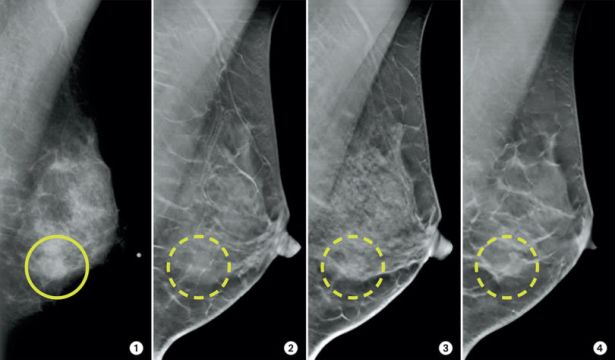

Several studies have found that 3-D mammograms find more cancers than traditional 2-D mammograms and also reduce the number of false positives. A false positive is when a mammogram shows an abnormal area that looks like a cancer but turns out to be normal.

Mammography is specialized medical imaging that uses a low-dose x-ray system to see inside breasts. A mammography exam, called a mammogram, aids in the early detection and diagnosis of breast diseases. We perform both screening and diagnostic mammograms

3D Mammography